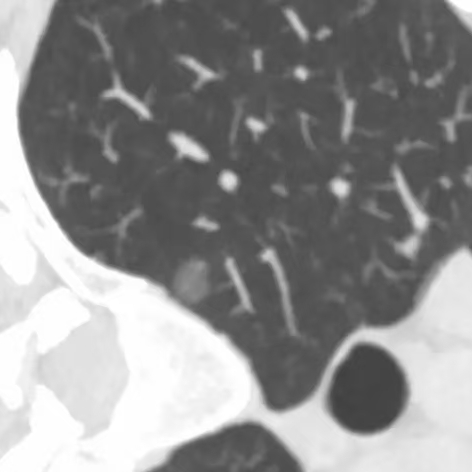

健康直通车: 健康是生命的宝贵财富,也是幸福生活的基石。为了更好地服务广大百姓,传播健康知识,葫芦岛市第二人民医院推出“健康直通车”专题栏目,将专业的医学知识以通俗易懂的方式传递给每一位市民,掌握科学的疾病预防方法,共同构筑健康中国的坚实基石。 什么是肺结节 肺结节是指肺内直径小于或等于3cm的类圆形或不规则形病灶,影像学表现为密度增高的阴影。大于3cm的称肿块。肺结节依其密度不同可分为实性结节、部分实性结节、磨玻璃结节,其中部分实性结节的恶性可能性最大,磨玻璃结节次之,实性结节尤其是小的实性结节结节最可能是良性的。 肺结节的常见病因 1、良性(约90%) 🔸 感染:结核、真菌、细菌性肺炎后遗留的瘢痕; 🔸 非感染:错构瘤(良性肿瘤)、炎性假瘤、血管瘤等。 2、恶性(约10%) 🔸原发性肺癌(如腺癌、鳞癌); 🔸转移性肿瘤(其他器官癌症转移至肺)。 如何根据影像判断肺结节性质 1、依据结节大小判断 🔸小于0.5cm的肺结节绝大多数都是良性的,属于微小结节。即使部分小于0.5cm肺结节是恶性的,但是适当的观察不影响预后。每年复查一次胸部CT就可以。 🔸大于0.5cm持续存在的纯磨玻璃结节,观察6个月,若持续存在,不管有无进展均多数是恶性的,视患者意愿,手术可以立即做也可观察至进展再做,不影响预后。 🔸大于0.8cm的部分实性结节恶性可能性非常大,应积极评估结节边缘毛刺、分叶、胸膜凹陷等征象。 🔸若实性部分大于0.5cm,恶性率显著提高。若在3~6个月随访期间实性部分增大或者总体部分增大,都可以考虑手术切除。而即使小于0.8cm的部分实性结节也需3个月就复查对比。 2、依据肺结节形态 如CT上提示病灶形态不规则、毛刺、分叶、胸膜凹陷、空泡征、血管集束征等,符合恶性肿瘤的征象。 🔸结节与正常肺组织之间界限非常清楚的恶性可能性大。 🔸结节密度不均呈混杂密度或均匀较大纯磨玻璃结节也基本是恶性的。 🔸有胸膜牵拉(不管是肺表面的脏层胸膜还是叶间裂部位的胸膜)的恶性可能性大。 🔸结节有浅分叶、细毛刺,密度较高而与周围肺组织边界不清的恶性可能性大。 🔸磨玻璃或混合磨玻璃结节存在小空洞的恶性可能性大。 🔸影像上似慢性炎表现,而没有炎症相关的其他异常,特别当所谓炎症区域内部或一侧与正常肺组织之间界限非常清楚的基本上是恶性的。 3、从结节发展情况来看 所有随访中增大进展的都需要考虑恶性可能,不进展而持续存在的纯磨玻璃结节也需考虑恶性。 葫芦岛市第二人民医院肺结节诊治中心孙振教授深耕肺结节领域四十余载,凭借对临床实践的执着钻研与深厚积淀,在肺结节精准诊断及鉴别诊断领域形成独到见解。他系统总结海量临床病例,创新性提炼出一套科学化、规范化的肺结节全周期诊疗体系,尤其在早期微小结节的影像特征识别、良恶性风险分层等方面积累了丰富经验,为众多患者提供了精准、高效的诊疗方案。 人民医院·人民名医 孙振 主任医师 三级教授 ·葫芦岛市第二人民医院胸外科主任、肺结节诊治中心主任 ·中国医科大学客座教授 ·原央企总医院著名胸外科专家 ·辽宁省医学会胸外科委员 ·辽宁省抗癌协会肺癌专业委员会委员 ·辽宁省细胞生物学学会食管癌专业委员会理事 ·主持多项科研成果获科技成果奖、科技进步奖、国家专科奖项 医学成就 从事胸外科临床工作近40年,担任胸外科首席专家及科室主任20余年,是我省胸外科领军人物,推动肺癌、食管癌等胸部肿瘤外科的规范化诊疗,在央企总医院牵头成立了肺结节诊疗中心,率先开展CT引导下肺内小结节定位切除,既确切完整切除肺内小结节,又降低肺功能损害。 专业特色 擅长肺癌、食管癌的外科手术和综合治疗,在各类高难度胸外伤手术治疗、胸腔镜微创手术、胸腺瘤手术及复杂并发症处理方面具有高深造诣,尤其擅长肺癌早期诊断,胸部小结节CT早期肺癌的鉴别等。完成各类高难度胸外科手术5000余例,其中微创手术占比达90%,治愈率达98%,多项业务填补省内空白。 开展的高难手术 胸腔镜肺部结节微创手术、肺癌根治术、食管癌根治术、各种纵隔肿瘤切除术、胸骨后甲状腺手术及胸部复合性外伤的抢救手术等。